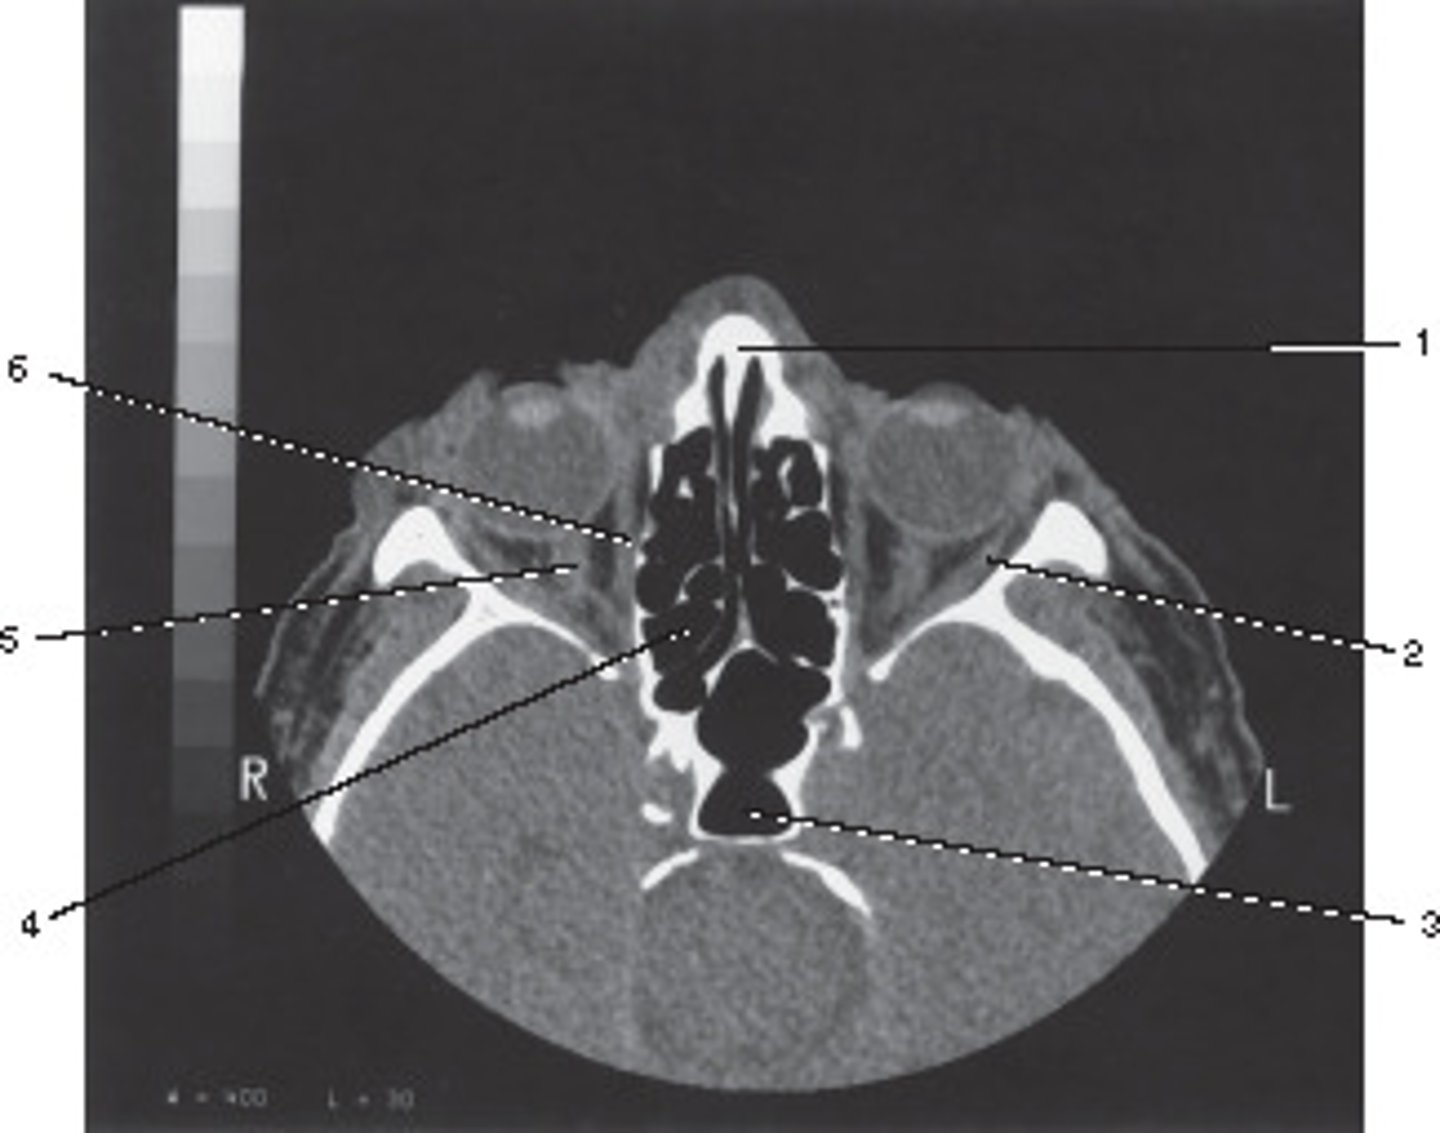

Dental Fillings; Metallic items cause star artifact

These streaking artifacts were most likely caused by:

<p>These streaking artifacts were most likely caused by:</p>

External Auditory Meatus

Number 3 corresponds to which of the following?

<p>Number 3 corresponds to which of the following?</p>

Which number corresponds to the vestibule?

<p>Which number corresponds to the vestibule?</p>